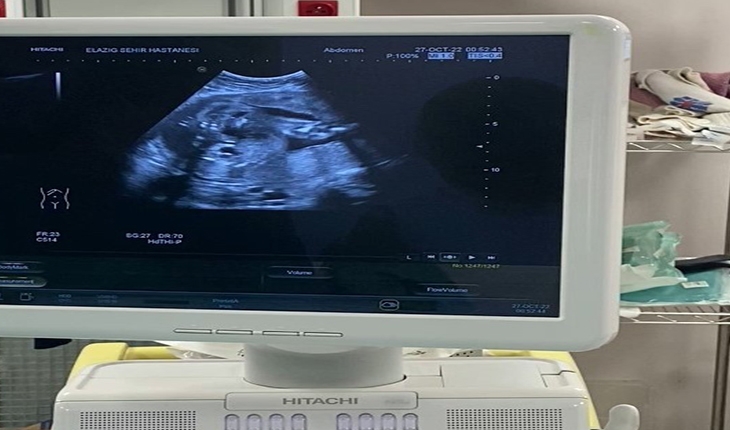

Ultrason eşliğinde Vesicoamniyotik Stent takılan bebeğin idrarını yapması sağlandı.

Şant yapılmasına karar verdiğimiz hastamıza sınırlı bir uyuşturma altında işlemimizi uyguladık. Ultrason eşliğinde yapılan işlem sonucunda bebeğimizin idrarını yapmasını sağladık” dedi.